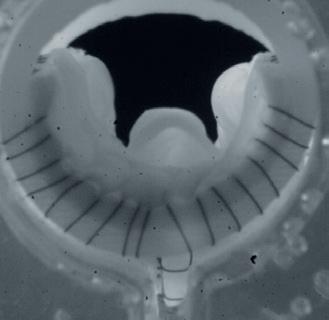

1. Pre-procedural venogram. 2. Venogram taken post-procedure 3. A representation of the clot removed. 4. The RevCore (top) and VenaCore (bottom) devices used

A man in his late 60s with a left iliac vein stent and revision two years prior was referred for consultation. The patient dis -

continued his anticoagulation two months before he was referred for consultation for severe left leg swelling. Duplex ultrasound confirmed a reoccluded left iliac venous stent. The decision was made to intervene with mechanical thrombectomy.

Procedural overview

Access was obtained in the superficial femoral vein and right internal jugular (IJ) vein under ultrasound guidance. A venogram demonstrated significant thrombus in the common femoral vein, profunda and extending into the external iliac vein. A .035” guidewire was inserted into the femoral vein and externalized through the access sheath. A ProtrieveTM sheath (Inari Medical) was inserted over the wire into the right IJ vein and advanced into the inferior vena cava. Next, the Triever20 catheter (Inari Medical) was inserted over the wire and directed to the profunda and common femoral vein. Aspiration with the Triever20 removed acute and sub-acute thrombus. Organized material could not be removed with aspiration. RevCore was then inserted over the wire into the occluded stent. Multiple clockwise and counterclockwise turns in conjunction with scrubbing the element within the stent resulted in successful clearance of nonacute thrombus. VenaCore was then introduced through the Protrieve sheath to clear the common femoral vein. Completion venogram demonstrated brisk cephalad flow. Total procedure time was 90 minutes.